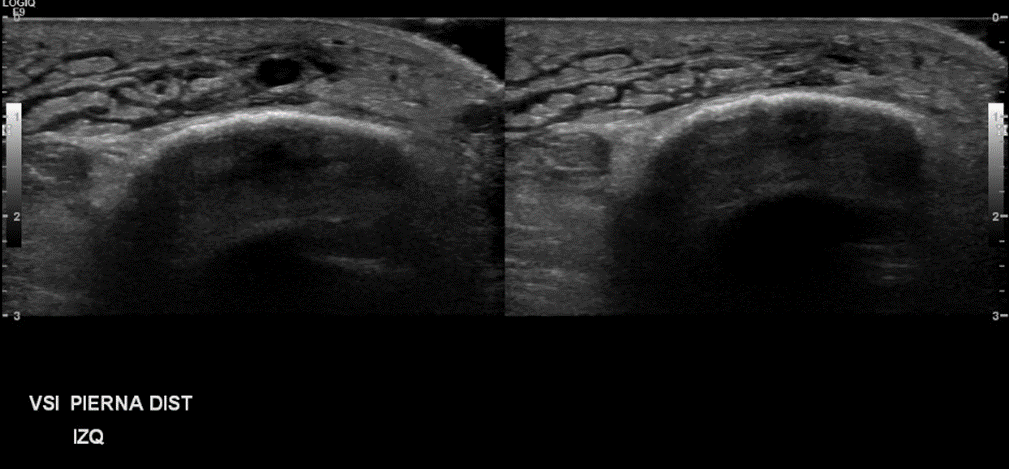

Examen realizado en posición semisentada. Protocolo TVP. IZQ:

• Incidentalmente se observa en la unión miotendínea distal del musculo gemelo medial un área heterogénea, hipoecogénica, con leve señal power Doppler, que desestructura el patrón muscular, sugerente de desgarro asociado a voluminoso hematoma interfacial que se correlaciona con el aumento de volumen palpable

• Sistema venoso superficial: Se observa permeabilidad de la vena safena interna y vena safena externa. No se observan signos de tromboflebitis. Incidentalmente se observa un desgarro del músculo gemelo medial con un hematoma interfacial secundario Impresión